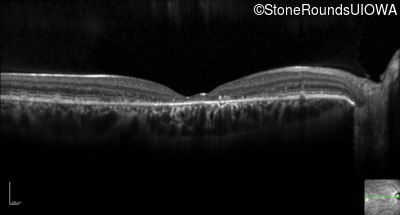

Optical Coherence Tomography - Left - 20/60

Exemplar / OCT Stack